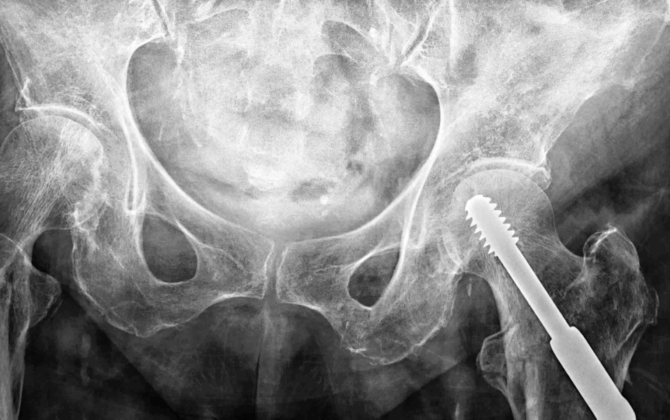

This program of research evaluates the performance of commonly used comorbidity measures (Charlson Comorbidity Index, Elixhauser and Multipurpose Australian Comorbidity Scoring System) on the prediction of 30-day and 1‑year mortality, 28 day re-admission, and length of stay in an older hip fracture population.